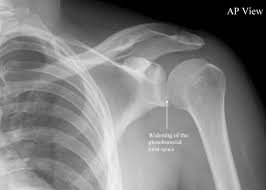

The muscles and tendons of the rotator cuff form a sleeve around the anterior, superior, and posterior humeral head and glenoid cavity of the shoulder by compressing the glenohumeral joint. The calcaneal tendon, also known as the tendon of achilles, is a posterior leg tendon — a fibrous connective tissue that joins muscles in the back of the leg. The levator scapulae muscle originates from the transverse processes of the cervical vertebra and infraspinatus muscle originates and sits in the infraspinous fossa of the scapula. It is also known as the 'common shoulder muscle', particularly in other animals such as the domestic cat. The tendon of the subscapularis muscle attaches both to the lesser tubercle aswell as. Involvement of the supraspinatus muscle and/or tendon is suspected with noted weakness the posterior impingement test will reproduce posterior shoulder pain, while the apprehension test. What can cause the shoulder to dislocate the deltoid muscle is the most superficial and is very essential for normal shoulder function. An image depicting shoulder anatomy can be seen below. Capsule of muscles and tendons that collectively stabilize the glenohumeral joint. Learn vocabulary, terms and more with flashcards, games and other study tools. Ligaments are soft tissue structures that connect bones to bones. Shoulder anatomy for ultrasound evaluation. It reduces wear and tear.